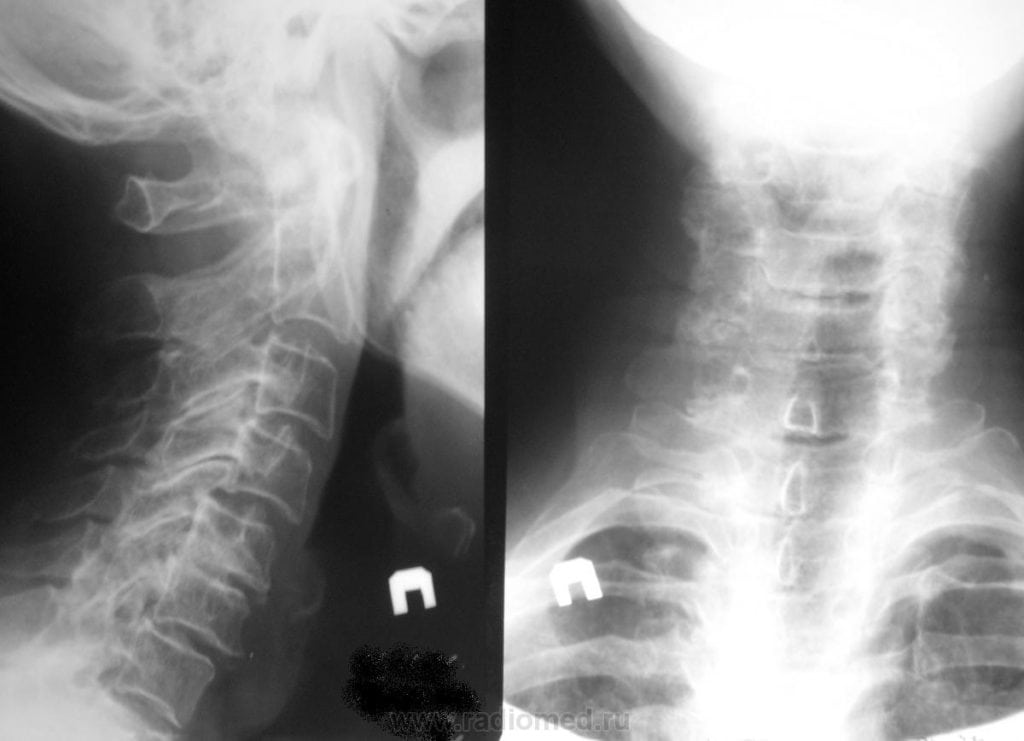

- рентгенография позвоночного столба и легких;

- КТ или МРТ;

Если терапевт, а именно к нему часто обращаются пациенты с кашлем, не обнаружил признаков инфицирования и присутствия посторонних предметов, то он проводит дальнейшее обследование больного. Обычно в таких случаях причиной становится или прием определенных препаратов для снижения артериального давления (Эналаприл, Лизиноприл), или остеохондроз. Диагностировать последний позволяет изучение рентгенографических изображений.

На них хорошо визуализированы истончившиеся межпозвонковые диски, сместившиеся позвонки, разросшиеся края костных пластинок. Пациент направляется для дальнейшего лечения к вертебрологу или неврологу.